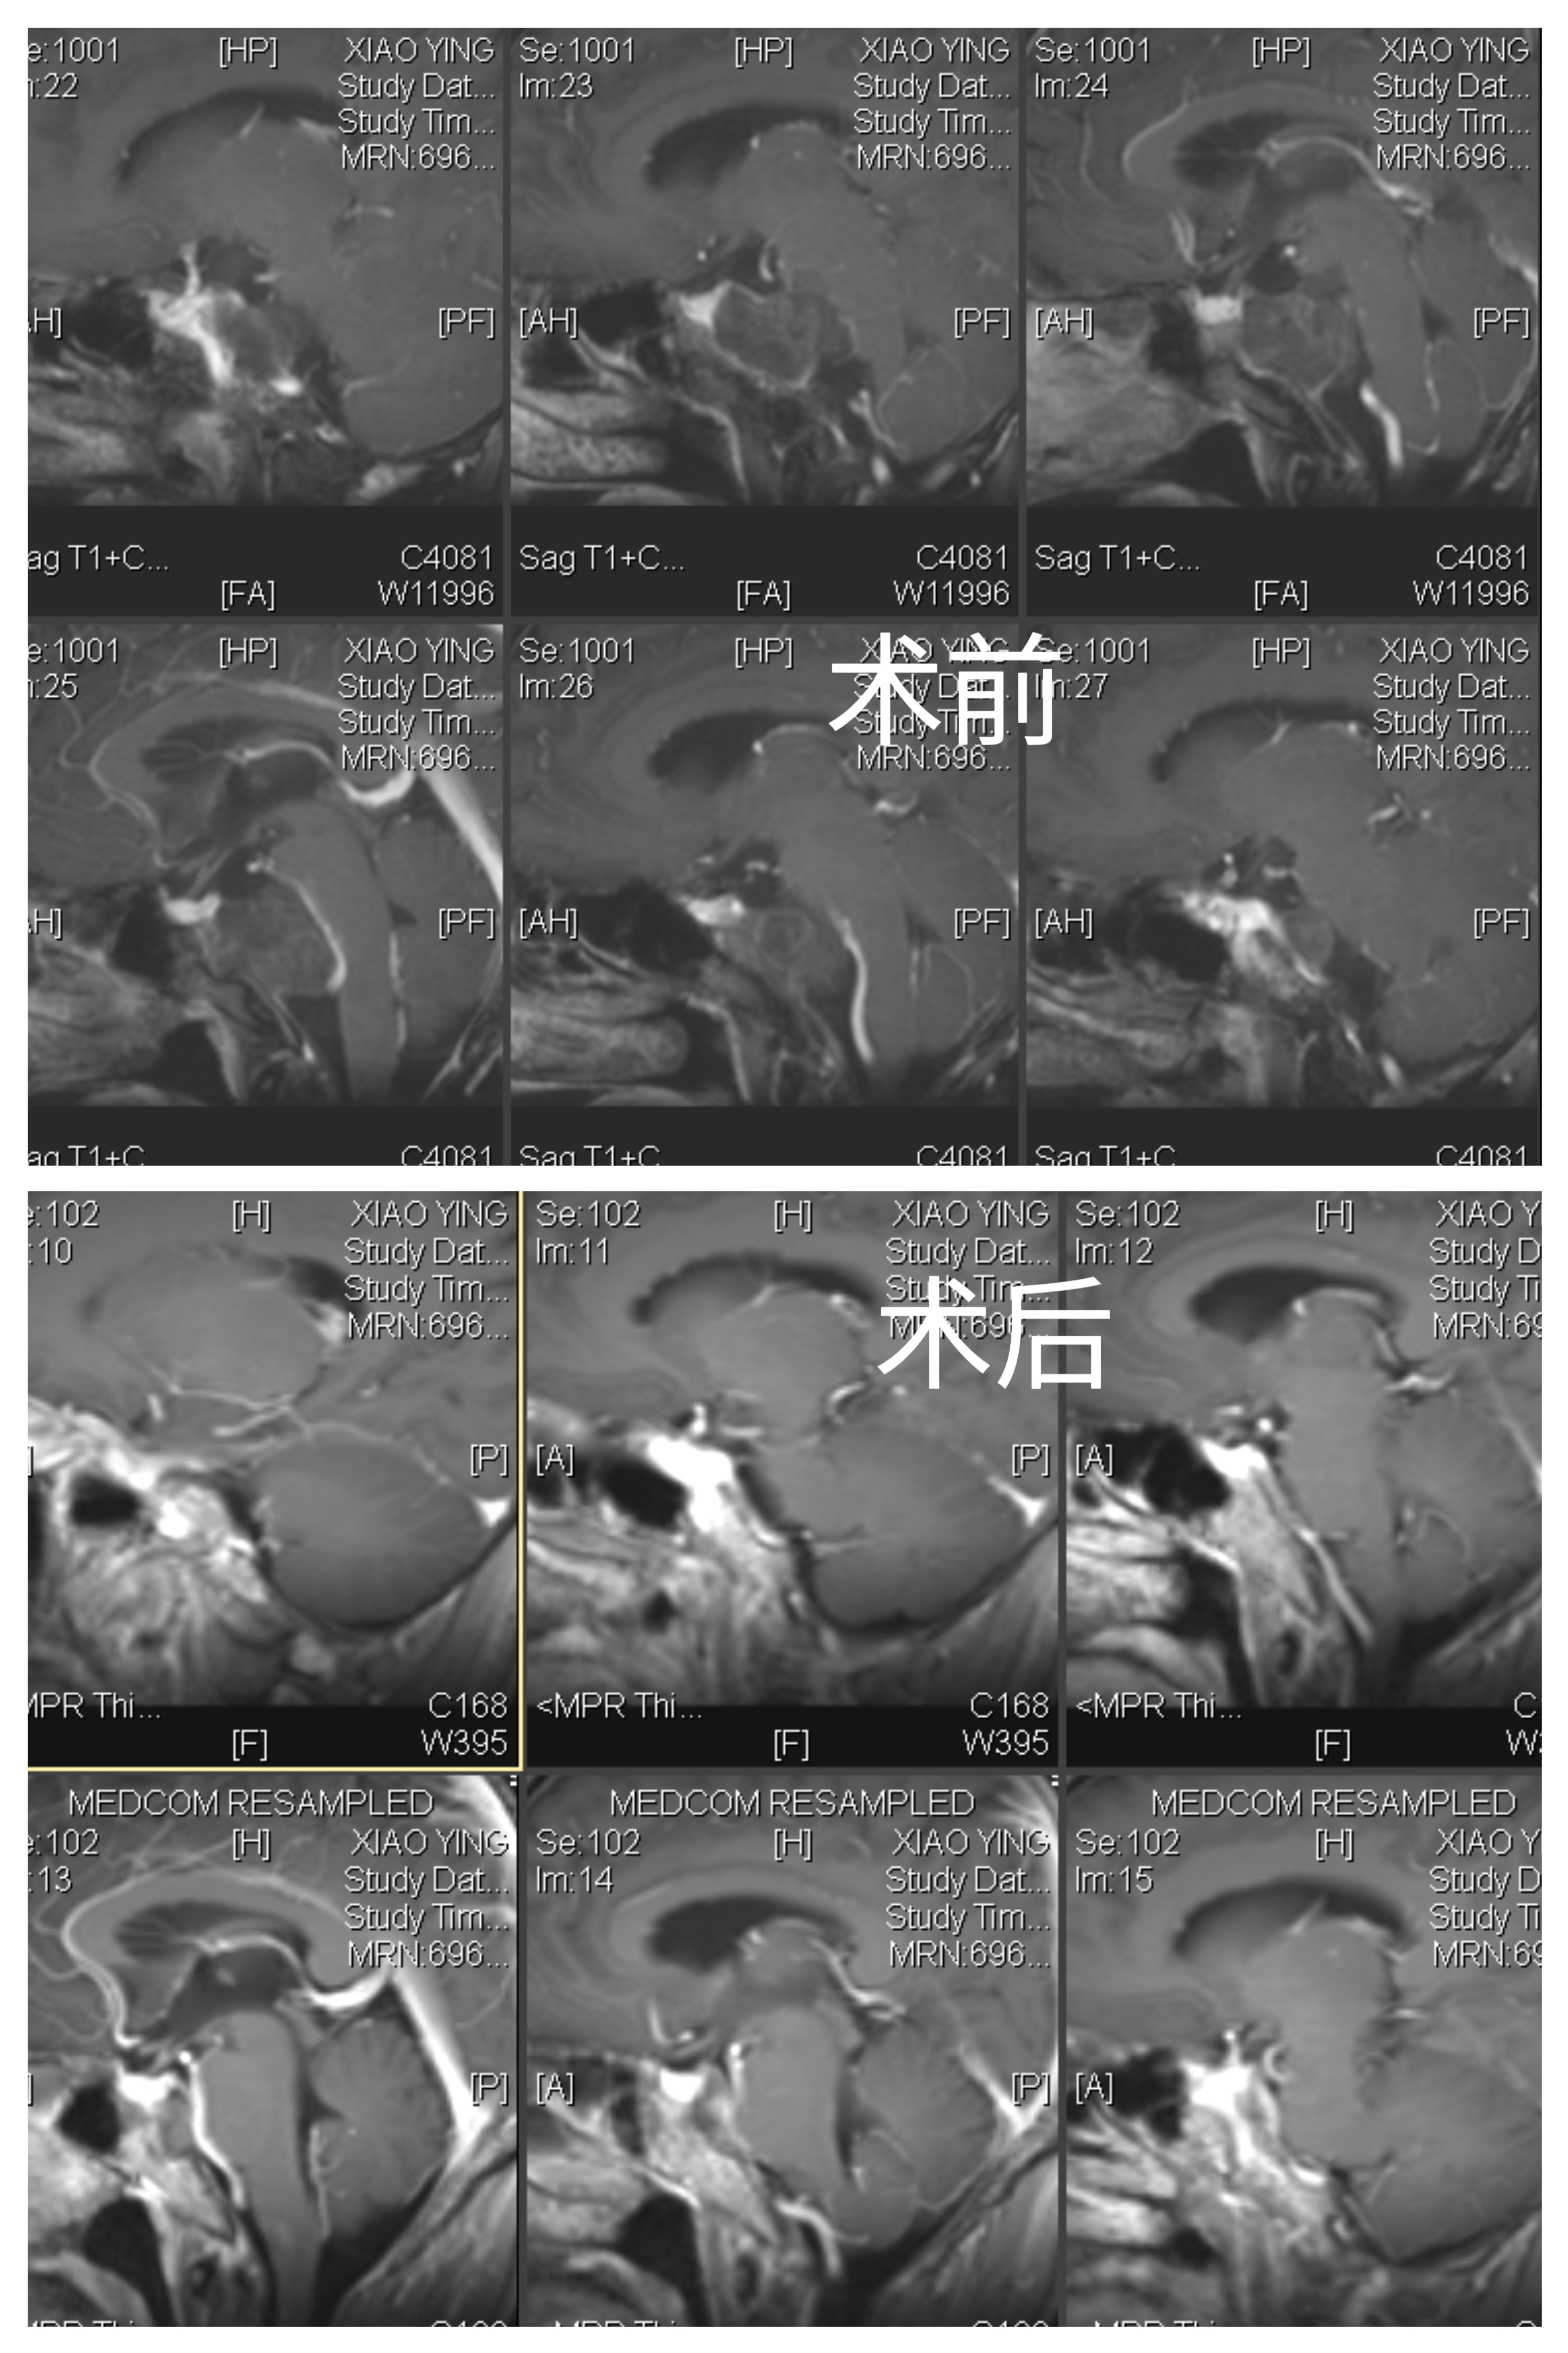

女性患者,56岁,因“视物重影4月”于2023-07-11入院。

入院诊断:斜坡脊索瘤

全麻成功后,病人仰卧位,头部向左侧偏转,右侧肩下垫枕。于右侧额颞部标记耳前颞下手术切口线。常规碘和酒精消毒,铺无菌单巾,沿切口线逐层切开头皮、帽状腱膜和颞肌,撑开皮肌瓣。止血后颅骨钻1孔,铣刀铣开取下骨瓣。

硬膜张力较高,色白,丝线悬吊骨窗硬脑膜止血。开放腰椎外引流,硬膜外抬起颞叶,予棘孔处电灼脑膜中动脉并切断。

魔钻磨除Kawase三角,见部分肿瘤位于硬膜外,肿瘤灰黑色,质软,血供丰富,使用环形刮匙和取瘤镊分块切除肿瘤,肿瘤包膜与颅底神经黏连严重,予以部分切除。弧形剪开颞部硬脑膜,脑组织博动正常。抬起颞叶,于滑车神后方切开小脑幕,电灼岩上窦,即见肿瘤,肿瘤灰红色,质软,血供一般,与双侧IV、V、VI、I、V颅神经及基底动脉粘连。显微镜下次全切除,部分肿瘤外包膜与上述神经血管黏连严重予以保留。创面电凝和速即纱压迫彻底止血。清点器械物品无误,硬膜下置引流管1 根,使用人工硬膜缝合硬脑膜,可吸收硬膜封合胶予以加固,复位并固定骨瓣,头皮和颞肌止血后,逐层缝合颞肌、帽状腱膜和头皮。